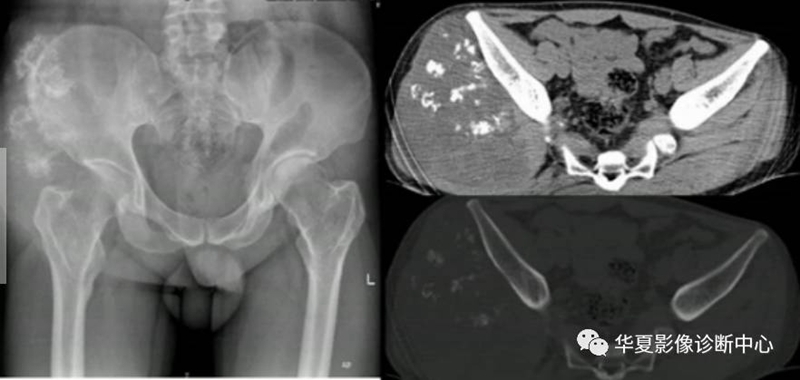

形态:环状,弧状,点状具有诊断意义,大小,良性者形态完整,境界清楚,密度均匀。恶性者相反。(如下图)